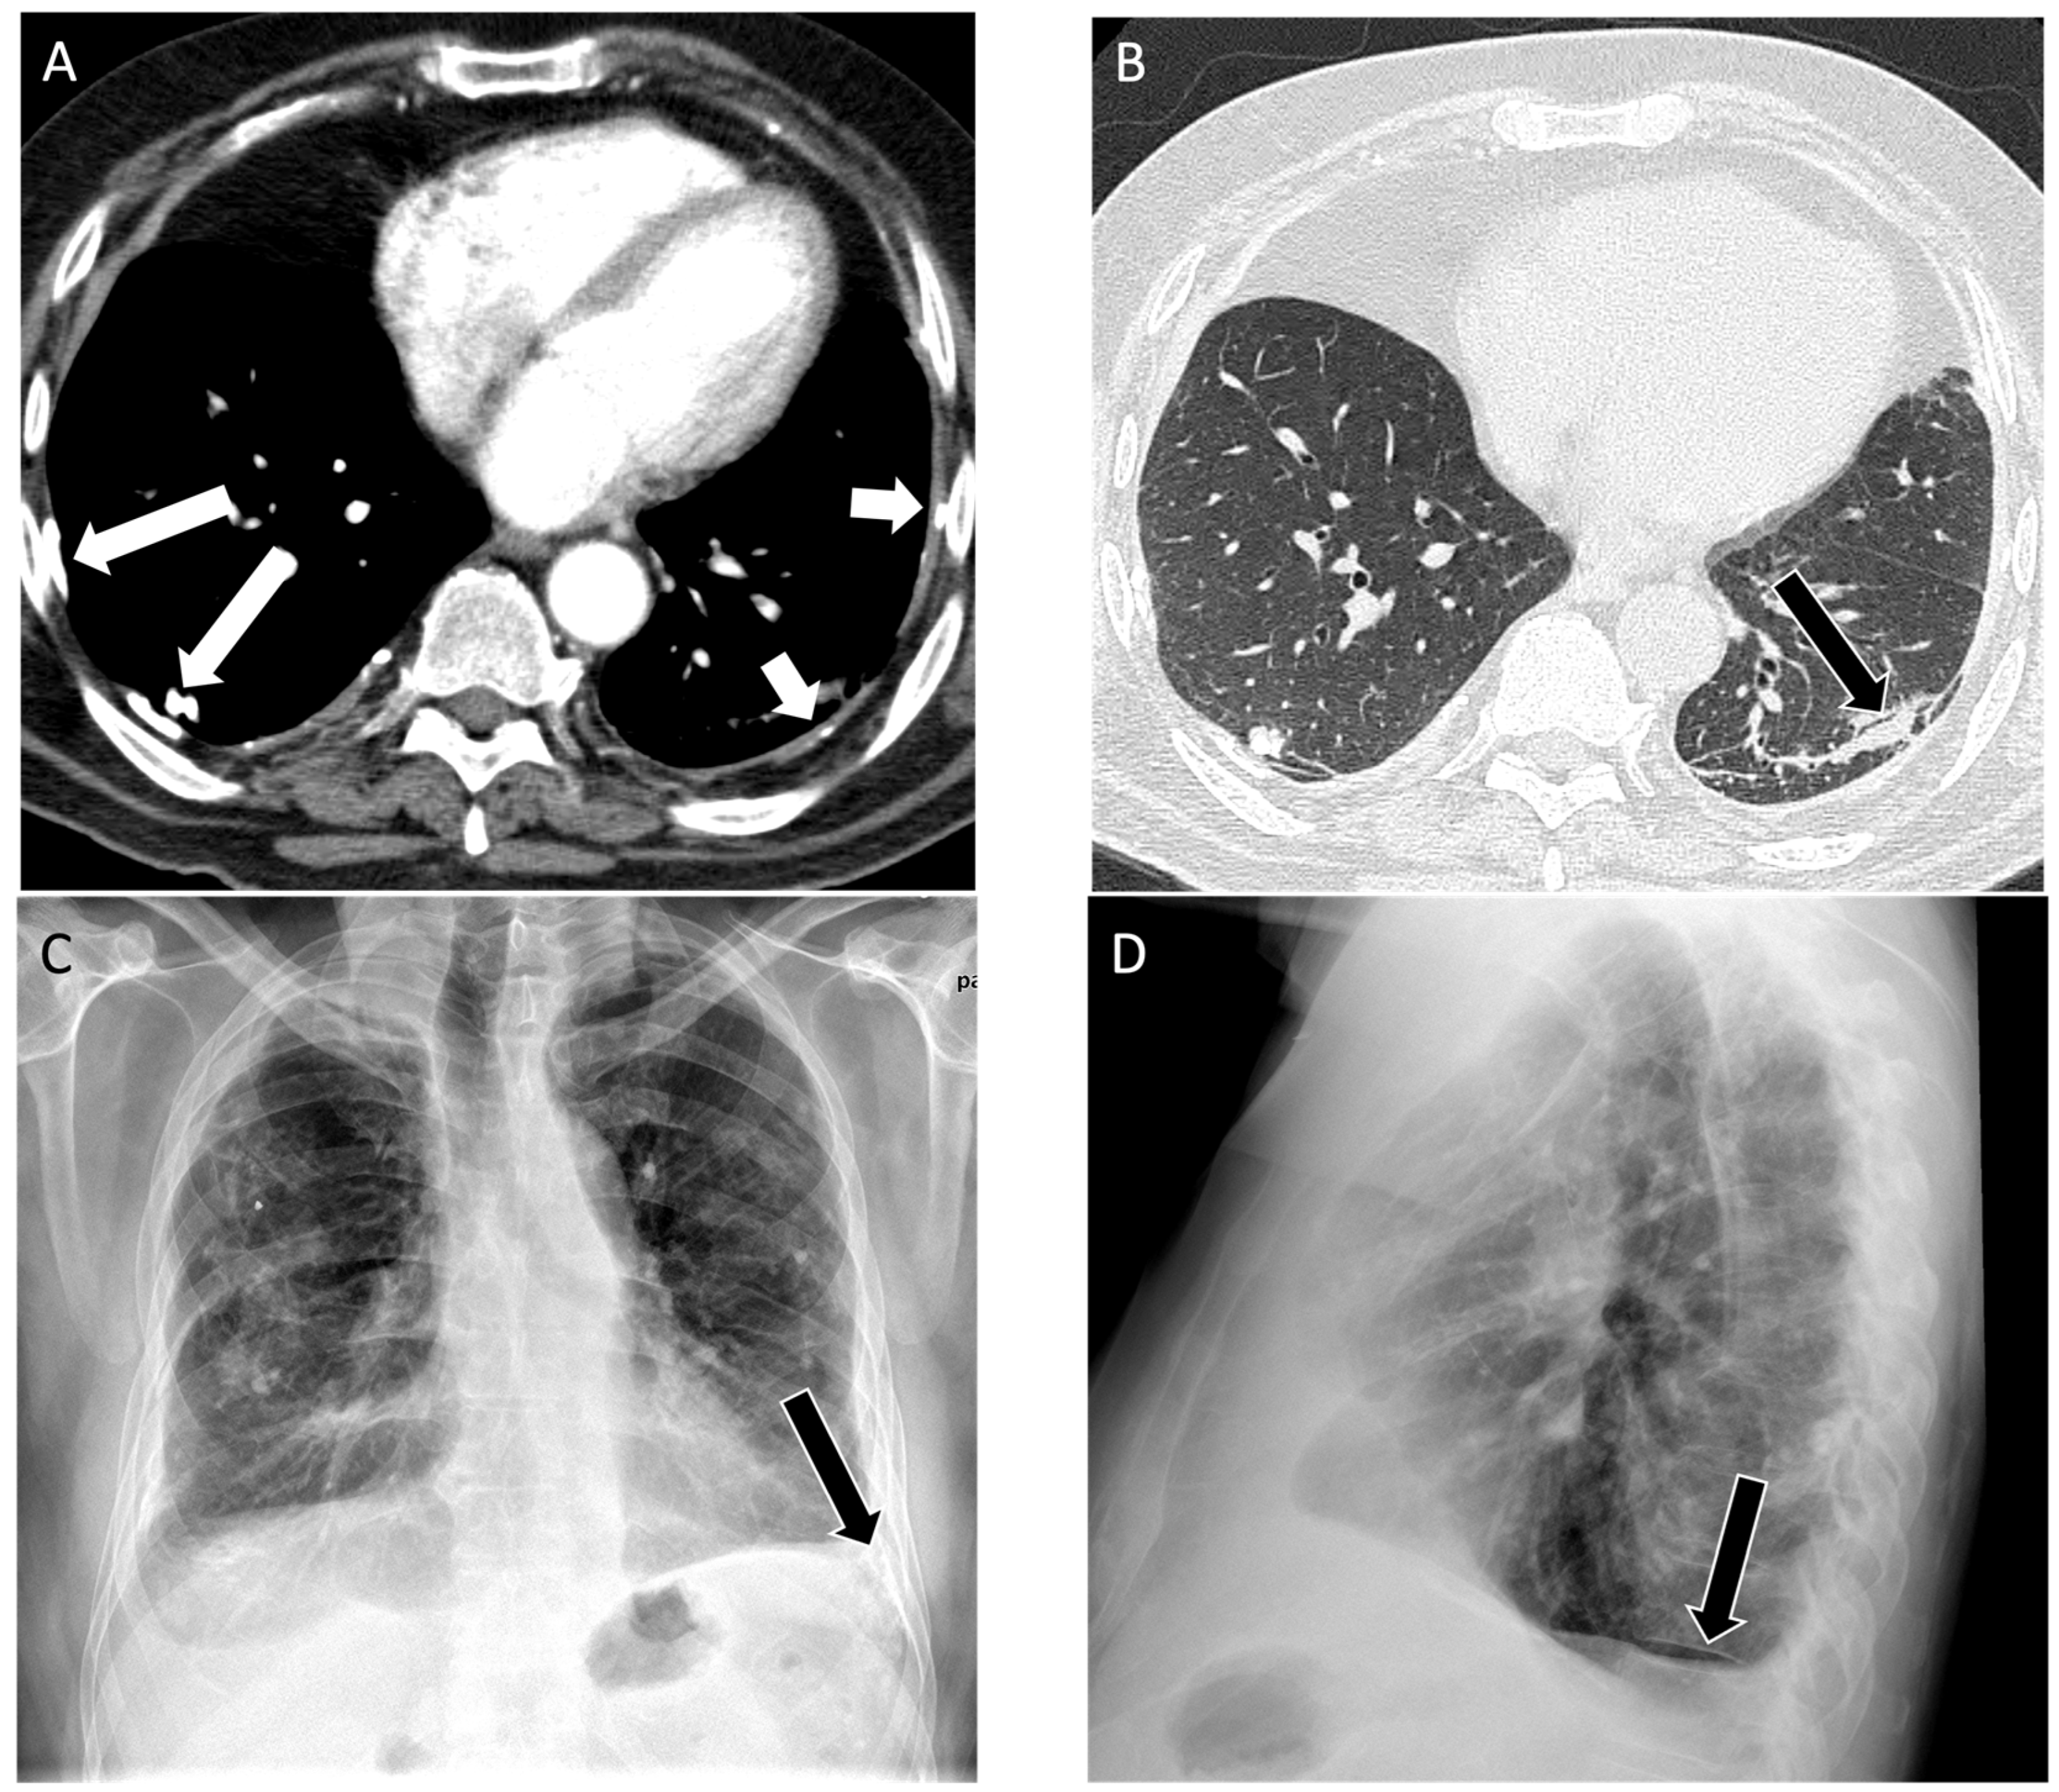

4.1. Silicosis

| Silicosis | Simple: small nodules in upper lung zone, pseudo-plaques, calcified lung nodules and/or lymph nodes [23,24] Complicated: conglomerate mass-like lesion, calcified lung nodules and/or lymph nodes, small peripheral lung nodules [25] Accelerated: similar to complicated silicosis [26] | Complicated: coalescence of silicotic nodules into a large mass [25] Accelerated: rapid progression (<10 years of exposure) [26] |